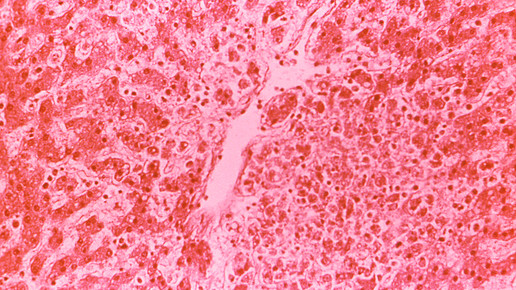

Weltweit erkranken nach WHO-Angaben jedes Jahr fast 400 Millionen Menschen an Denguefieber. Erkrankte haben oft heftige Kopf-, Augen- und Gliederschmerzen und müssen sich übergeben. In schweren Fällen kommt es zu inneren Blutungen und Gefäßschäden.